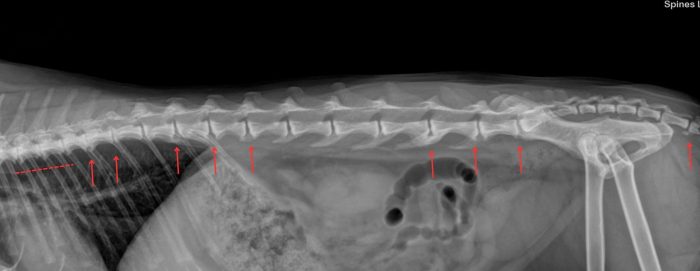

In de onderstaande foto’s is het verschilt te zien tussen een ruggenwervel van een kat zonder en met artrose. Hierbij is de artrose aangegeven met rode pijlen. Bij een röntgenfoto beoordeeld de arts of er aanwezigheid is van een versmalling van de gewrichtsspleet, wat duidt op een afname van het kraakbeen.